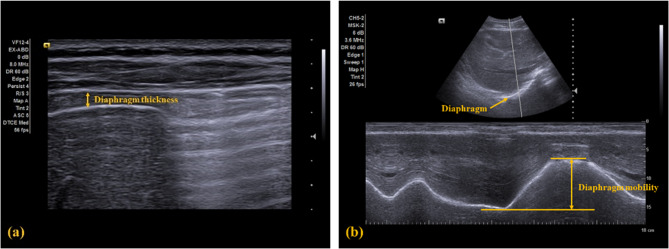

Methods: A total of 33 participants with CNP were randomized into the DMR and sham release group (SG), and received the allocated intervention twice a week for 2 weeks. The DMR group received a firm pressure release technique at the 7th to 10th subcostal region along with deep breathing, while the SG group received the same technique with light touch instead. Primary outcomes including pain, disability, and diaphragm function, and secondary outcomes including neck range of motions, strength, and chest expansion were performed before and after the intervention for all participants.

Results: After receiving 4 sessions of intervention, the DMR group demonstrated clinically significant improvements in pain and cervical range of motion, along with potential clinically improvements in diaphragm mobility. In the SG group, only pain showed a clinical significant improvement. Cervical strength and chest expansions showed potential clinical improvements in both groups.